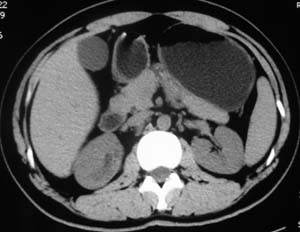

以下是引用子期在2010-3-19 20:47:00的发言:[br]血管畸形的ct增强应该有明显强化,本例并不相符合。本例双肾局部的略低密度影,累及肾盂,局部皮质明显变薄、内陷,增强扫描有轻度的强化,应考虑为炎性病变,患者为年轻男性,累及双肾的感染以结核较常见,可以没有明显的临床症状,尿中有时候也并不能查出什么;肾脓肿常有明显感染中毒症状,本例不符,另外一般的肾盂肾炎或肾小球肾炎通过小便就可确诊,其它还不能排除的是黄色肉芽肿性肾盂肾炎,然而单凭ct一般也很难鉴别。